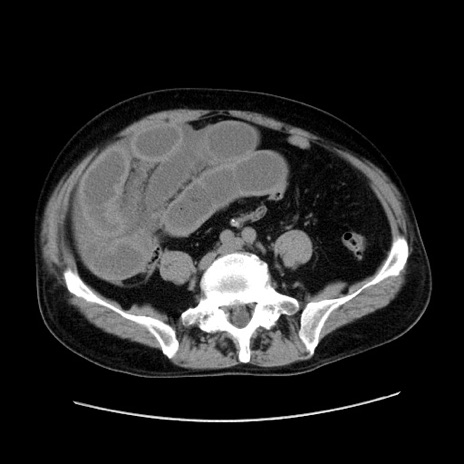

症例30(横断像)

【症例】80歳代男性

【主訴】臍周囲痛

【現病歴】約6時間前から臍下部痛が出現。次第に腹部膨隆・背部痛も生じてきたため来院。背部痛の場所は変化しない。

【既往歴】腎盂腎炎

【身体所見】意識清明、BT 36.3℃、BP  131/87mmHg、P 87bpm、SpO2 100%(RA)、臍周囲自発痛・圧痛あり、反跳痛なし、自発痛部位に一致して板状硬あり、腹部膨隆、腸雑音減弱、CVA tenderness両側陰性。

【データ】WBC 19600、CRP 0.33